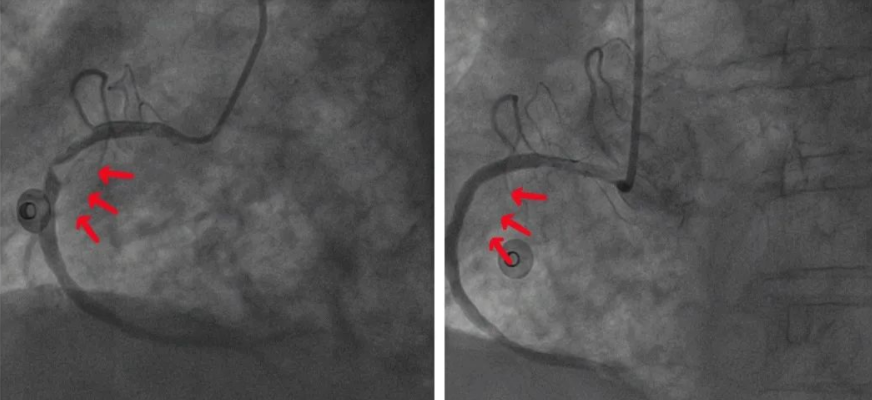

岳池县人民医院心血管内科侯兴志、张钰彬主任带领何青松、罗雪、郑加、宋志平等我院介入团队,在呼吸机机械通气的支持下快速完成冠状动脉造影及冠状动脉支架植入术。

冠状动脉造影发现莫婆婆回旋支闭塞,右冠状动脉、前降支重度狭窄,介入团队快速制定了介入方案,通过多学科合作实施手术,在介入放射科、心血管内科、急诊重症医学科的通力协作下手术过程顺利,上演一场与死神相搏的生死较量。